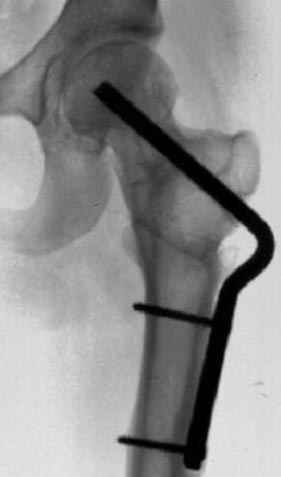

Djoldas Kuldjanov 23 Ноябрь 2004, 18:21

пластическая модель; и коррекция бедра аппаратом Илизарова.

Имею другие снимки тоже, получится как отчет о моей работе.

хотя даже если бы и инфекция , то nail exchange с рассверливанием канала - вариант дебрайдмента) Я думаю, что последовательность развития событий:

Узкий к-м канал - тонкий гвоздь- усталостный перелом дистальных винтов - развитие нестабильности и как ее результат остеолиз вокруг гвоздя - деформация анатомической оси бедра. Похоже, что я понял почему аппарат, а не новый гвоздь:-)